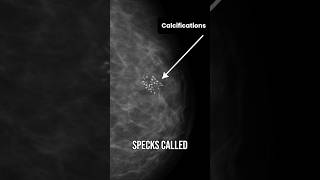

Dcis Stage 0 Breast Cancer